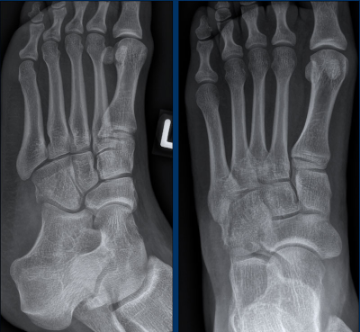

X-ray 1 X-ray 2